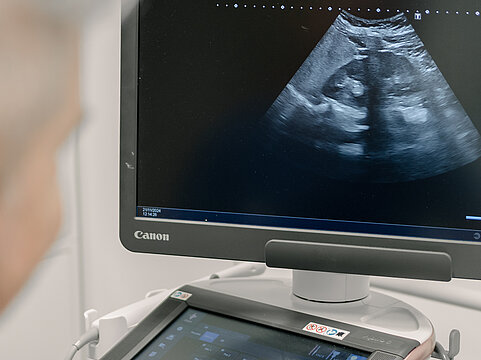

• Abtasten der Prostata, Ultraschall der Nieren, der Harnblase, Ultraschall der Hoden